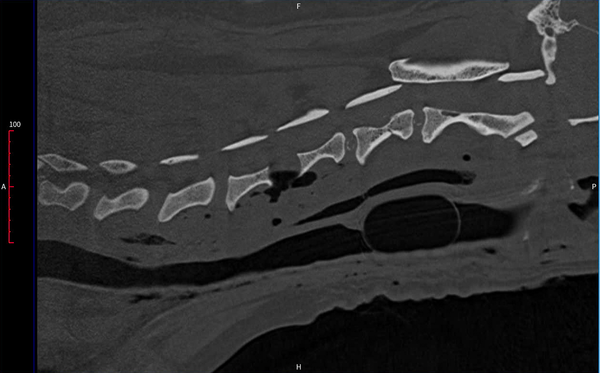

CT-scan thú y cho thấy đĩa đệm C4 – C5 thoát vịchèn ép tủy sống cổ, gây ra các biểu hiện thần kinh rõ rệt.

• CT- scan: Xác định đĩa đệm C4 – C5 thoát vị, chèn ép lên tủy sống cổ, gây ra triệu chứng thần kinh.

Hình ảnh CT thể hiện đĩa đệm cổ bị phồng ra phía sau, làm biến dạng tủy sống. Ngoài ra, các đĩa đệm lân cận cũng có dấu hiệu thoái hóa — cho thấy bệnh thoát vị đĩa đệm tiến triển mạn tính.